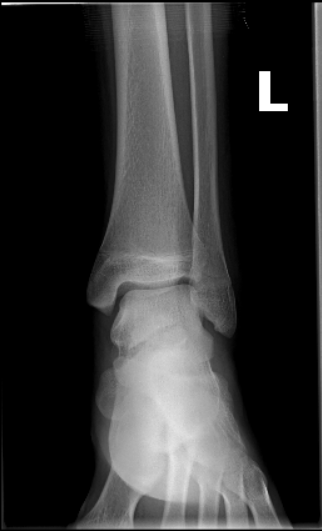

- Úhly dolní končetiny jsou v této verzi DICOM prohlížeče upraveny a nyní zobrazují také laterality úhlů. Lateralitu úhlů je možné určit pomocí pravého postranního panelu v „Pracovní sadě nástrojů měření“, rozbalovacího menu „Lateralita“ v záložce „Úhly dolní končetiny“. Po naměření úhlů dolní končetiny jsou zobrazeny tyto úhly:

- HKA – hip-knee-ankle angle

- mLDFA – mechanical lateral distal femoral angle

- mPTA – medial proximal tibial angle

- JLCA – joint line convergence angle